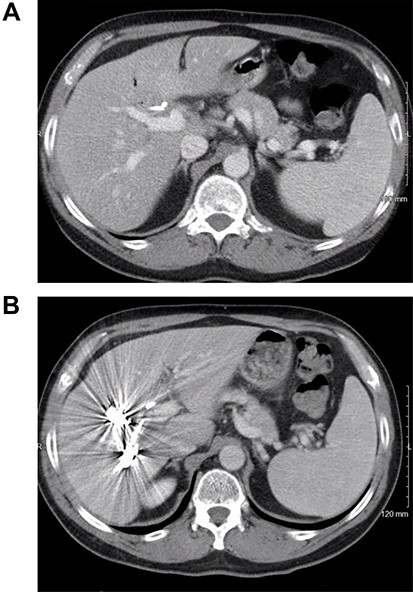

The patient received systemic chemotherapy with gemcitabine and cisplatin. After more than 2 months, he developed grade 3 neuropathy and experienced several episodes of cholangitis with liver abscess and bacteremia requiring multiple stent exchanges, and systemic therapy was discontinued. He then received trial-based immune check point inhibition with ipilimumab and nivolumab. There was good radiological (Fig. 1B) and tumor marker response (CA 19–9 7.05 U/ml). Immunotherapy had to be stopped after 10 months due to grade 3 autoimmune hepatitis. He was treated with oral steroids and immunosuppression with mycophenolate mofetil, resulting in the normalization of liver function tests. A R0 resection was now deemed a possibility, with a goal of best tumor control and long-term biliary decompression. He underwent right portal vein embolization after which his left lobe future liver remnant grew from 28 to 45% at a kinetic growth rate of 5.6% per week (Fig. 2). He underwent extended right hepatectomy with radical cholecystectomy, portal and hepatic artery lymph node dissection, and Roux-Y hepaticojejunostomy biliary reconstruction (Fig. 3). Pathology examination revealed a 6.5-cm gallbladder and hepatic tissue mass with xanthogranulomatous inflammation and nodular fibrosis, without residual viable tumor, margins free of carcinoma and 0/17 lymph nodes involved, consistent with an ypT0N0M0 gallbladder cancer, R0 resection. After an initial postoperative surgical site infection, he has now fully recovered and is disease-free at 10-month follow-up.

CT scan image of the liver: (A) small left lobe prior to portal vein embolization; (B) left lobe hypertrophy after right portal vein embolization.